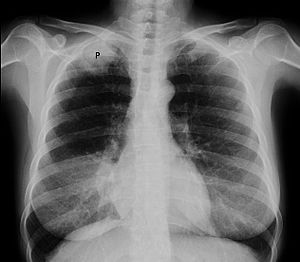

Chest radiograph showing a Pancoast tumor (labeled as P, non-small cell lung carcinoma, right lung), from a 47-year-old female smoker.

Diagnosis of Pancoast tumor is usually made after evaluating clinical symptoms and imaging. Chest X-ray is a good screening test even though Chest CT scan can provide a better resolution and extent to which internal organs are being compressed.[citation needed]